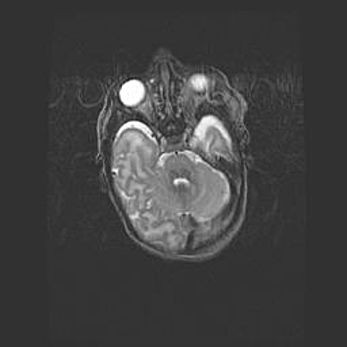

Лейкомаляция с кистозно-глиозной дегенерацией головного мозга.

Возраст: 2 месяца 25 дней

Вес: 6400 г

Окружность головы: 40 см

Срок гестации: 41 неделя

Лейкомаляцию относят к ишемически-гипоксическим повреждениям головного мозга, диагностируемым у новорожденных. При лейкомаляции в головном мозге обнаруживают очаги некроза, возникшие после тяжелой гипоксии и нарушения кровотока. В процессе морфогенеза очаги проходят три стадии: 1) развития некроза, 2) резорбции и 3) формирования глиозного рубца или кисты. Перивентрикулярная лейкомаляция (ПЛ) встречается примерно в 12% случаев среди новорожденных, обычно – у недоношенных детей, причем, частота ее зависит от массы, с которой младенец появился на свет. Наибольшее число малышей страдает лейкомаляцией, если масса при рождении 1500-2500 г.